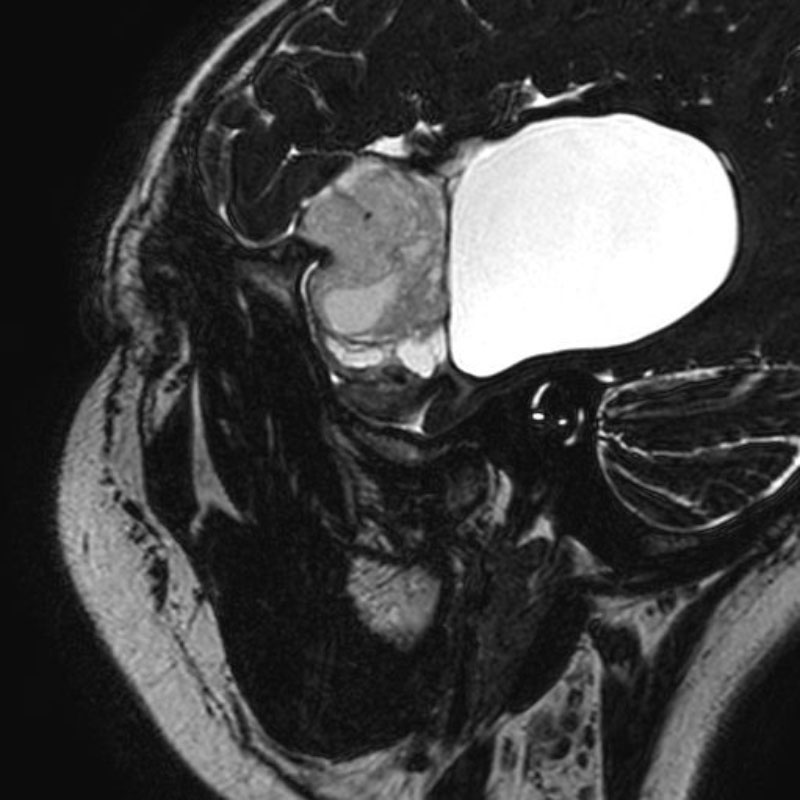

5月15日(金)

右顔面痙攣

微小血管減圧術

岩井/古部

脳動脈瘤(Acom)

クリッピング術

松田/濵田/元永